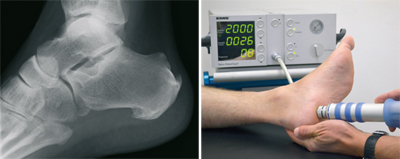

Calcaneal

The plantar Calcaneal (at the bottom of the heel) is caused by an overload of the longitudinal arch braced fascia. Connective tissue, excessive loads, malposition, but also overweight may be responsible. The congestion between the heel bone and the attachment site of this fascia is an increasing tissue damage associated with a ossification, called Calcaneal. Not the spur itself, but this tissue damage is causing the pain. They start appearing when putting pressure on it, but later also at rest. First of all the available treatments is the supply of special arch supports. Also injections directly to the Calcaneal, have their value. The shock wave therapy as proved to be very risk-free, which is carried out in our practice. Alternatively, X-ray irradiation effect healing.

Failure of all non-operating activities is also a surgical treatment option. Via a small cut at the inner edge of the heel fascia is nicked, the voltage decreases and the tissue damage can heal.

The posterior Calcaneal (back of the heel) is caused by an overload of the Achilles tendon at the base. Through the underlying calcaneus is very little space between the skin and bone. Pain or pressure damage may be the result. The beginning should be a consistent pressure relief by appropriate footwear. If this wont help the spur has to be removed surgically. For this purpose, it can sometimes be necessary to replace the approach of the Achilles tendon and fix it back to the heel bone.